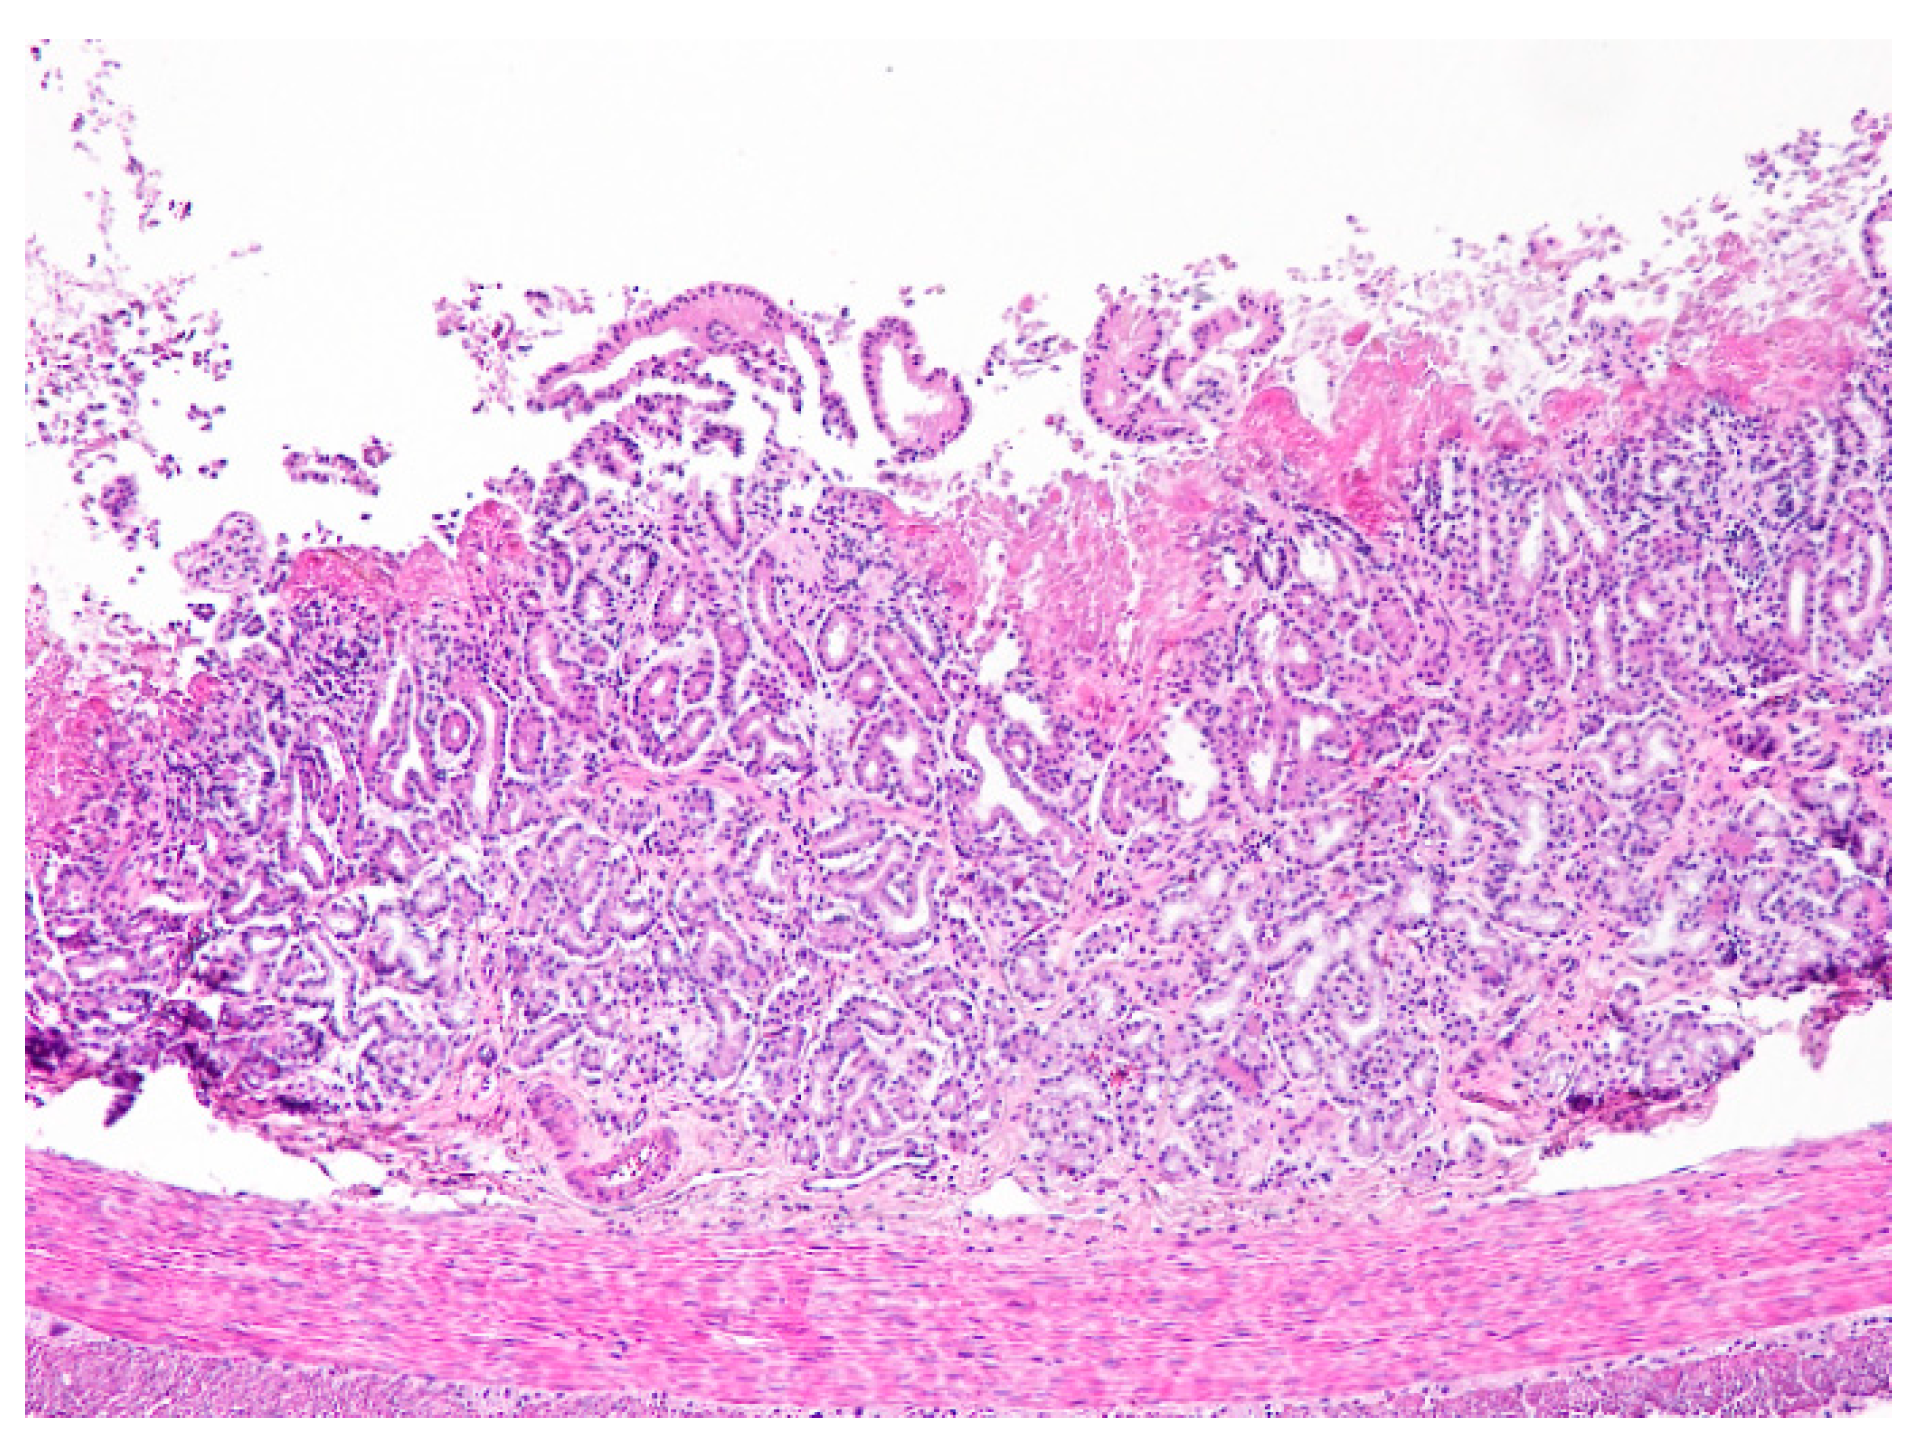

The following microscopic lesions were observed: Liver: severe generalized perilobular haemorrhagic necrosis (Figure 3 and Figure 4). Discrete infiltration by mononucleated inflammatory cells, mainly macrophages and lymphocytes, around portal triads. Fine brown pigment in the cells of the portal bile ducts. Spleen: diffuse necrosis of the entire red pulp revealed by deposition of fibrinoid acidophilic material drawing serpiginous patterns in the parenchyma (Figure 5). The regular presence of lymphoid follicles around central arterioles. Pancreas: interlobular oedema and necrosis of adipocytes, both intralobular and interlobular. No changes were present in the secretory cells. Stomach: no significant changes were observed. Small intestine: Necrotic enteritis, particularly in the duodenum, with loss of villi and deposition of fibrin in the proximal mucosa (Figure 6). Kidneys: the areas of surface retraction in both kidneys corresponded to segmental fibrosis affecting cortex and medulla. In these areas, there was a loss of tubules and glomeruli, which were moderately congested. No microbial agents were identified in any organ and the results of the microbiological analysis were also negative.

Figure 6. Duodenum. Necrotic enteritis affecting the upper mucosa. Note the absence of villi and the eosinophilic deposits of fibrin in the upper mucosa. The intestinal glands are disorganized and the inflammatory infiltrate of the mucosal lamina propria by mononuclear cells (lymphocytes mostly) is scant (H&E, 100×).